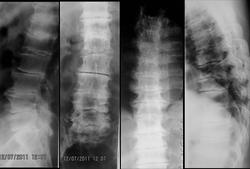

Пол пациента: Мужской пол Тип патологии: Другое Область исследования: Скелетно-мышечная система Методы исследования: RgКТ Вот такой интересный пациент. Анамнез... без особенностей. Жалобы на боли в спине. Вопрос. А не системное ли это заболевание? Или так: только ли дегенерация? С уважением, Коробейников А.В. https://radiomed.ru/sites/default/files/styles/case_slider_image/public/user/565/opisanie_rentgen.jpg?itok=Lfoa_utV https://radiomed.ru/sites/default/files/styles/case_slider_image/public/user/565/kt.jpg?itok=OJ7donj3 https://radiomed.ru/sites/default/files/styles/case_slider_image/public/user/565/opisanie_kt.jpg?itok=4YlLWLqb ID:17348 Ср, 07/12/2011 - 18:46 #1 v1tal Не на сайте Был на сайте: 5 лет 2 месяцев назад Зарегистрирован: 07.06.2008 - 19:41 Публикации: 1779 Думается мне с этической точки зрения ФИО пациента и врача следует убирать, всегда при публикации материала. "Знаешь, у некоторых врачей есть комплекс мессии — им необходимо спасать мир. А у тебя комплекс Рубика — тебе необходимо решать головоломки." Ср, 07/12/2011 - 20:59 #2 ЛГ Не на сайте Был на сайте: 9 лет 3 месяцев назад Зарегистрирован: 06.01.2010 - 12:31 Публикации: 3523 Про пациента - согласна. А врача ФИО - так автор и есть тот врач... Стрелочкой - на мой взгляд, последствия дисцита. А про системность - не знаю, 50/50. https://www.youtube.com/channel/UCBGxoBUOqUT_bFhSeUgtWEw Чт, 08/12/2011 - 14:14 #3 maren Не на сайте Был на сайте: 8 лет 1 месяц назад Зарегистрирован: 18.10.2011 - 10:26 Публикации: 7 соглашусь насчет дисцита. помимо снижения определяется деформация суставных поверхностей тел позвонков, блоки из-за клювовидных разрастаний. смещение L2 кзади............может деформирующий спондилоартроз. Поликлиника: ускоренные курсы по обмену опытом между больными Пт, 09/12/2011 - 13:38 #4 Kuzmitch Не на сайте Был на сайте: 13 лет 6 дней назад Зарегистрирован: 01.10.2010 - 18:20 Публикации: 171 Здравствуйте. Удивляет снижение высоты всех дисков. Может быть действительно, какая-нибудь аномалия развития дисков? Втр, 03/01/2012 - 23:38 #5 anuta Не на сайте Был на сайте: 14 лет 1 месяц назад Зарегистрирован: 11.10.2011 - 18:45 Публикации: 46 дегенеративно-дистрофические изменения по всему позвоночнику.Не позавидуешь - мужик-то вроде не старый ( 50 лет всего!)

Про пациента - согласна. А врача ФИО - так автор и есть тот врач... Стрелочкой - на мой взгляд, последствия дисцита. А про системность - не знаю, 50/50.

соглашусь насчет дисцита. помимо снижения определяется деформация суставных поверхностей тел позвонков, блоки из-за клювовидных разрастаний. смещение L2 кзади............может деформирующий спондилоартроз.

Здравствуйте. Удивляет снижение высоты всех дисков. Может быть действительно, какая-нибудь аномалия развития дисков?

дегенеративно-дистрофические изменения по всему позвоночнику.Не позавидуешь - мужик-то вроде не старый ( 50 лет всего!)